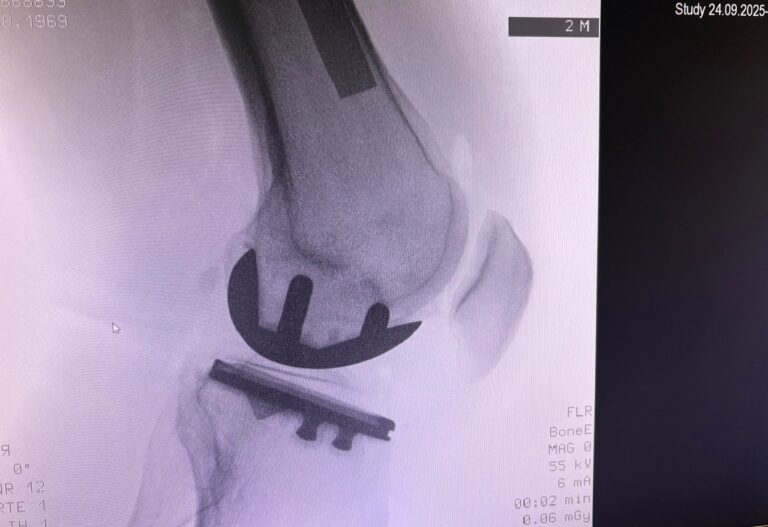

Η ημιολική αρθροπλαστική γόνατος (partial / unicompartmental knee replacement) είναι επέμβαση όπου αντικαθίσταται μόνο το φθαρμένο διαμέρισμα του γόνατος και όχι ολόκληρη η άρθρωση.

Πλεονεκτήματα

- Διατηρείται το υγιές οστό & οι σύνδεσμοι

- Πιο φυσική αίσθηση γόνατος

- Λιγότερος πόνος μετεγχειρητικά

- Ταχύτερη αποκατάσταση

- Ευκολότερη μετατροπή σε ολική αρθροπλαστική αν χρειαστεί στο μέλλον

Πώς γίνεται

- Μικρότερη τομή από την ολική

- Αντικατάσταση μόνο του πάσχοντος διαμερίσματος

- Διάρκεια επέμβασης: ~1 ώρα

- Συχνά βάδιση από την ίδια ημέρα

Ημιολική vs Ολική αρθροπλαστική

| Χαρακτηριστικό | Ημιολική | Ολική |

| Έκταση επέμβασης | Μικρή | Μεγάλη |

| Αίσθηση γόνατος | Πολύ φυσική | Καλή |

| Ανάρρωση | Ταχύτερη | Πιο αργή |

| Κατάλληλη για όλους | Όχι | Ναι |

| Διάρκεια εμφυτεύματος | Πολύ καλή (σε σωστές ενδείξεις) | Άριστη |